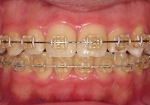

☆審美ワイヤー(光拡散型)の使用例と

ホワイトワイヤー(コーティング)での治療例

低摩擦クリア矯正装置

設定した治療ゴールにすばやく到達するためには,歯を低摩擦(ローフリクション)で移動させることが重要です.当院では「ローフリクションtypeのブラケットシステム」を採用しています.